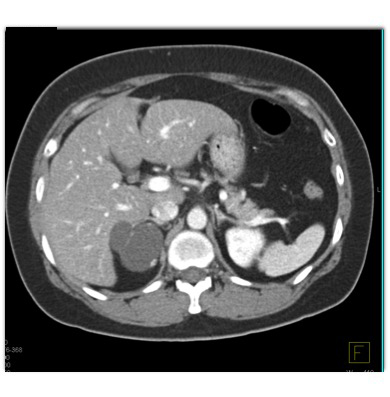

The most likely diagnosis for the right adrenal mass is?

adrenal cyst

adrenal hematoma

adrenal lymphangioma

adrenal carcinoma